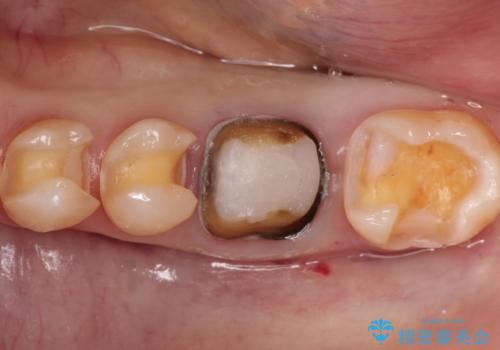

- 金属を外して白い歯を手に入れたいとのことで来院されました。

根管治療歯は破折防止のため速やかに被せ物が必要になります。